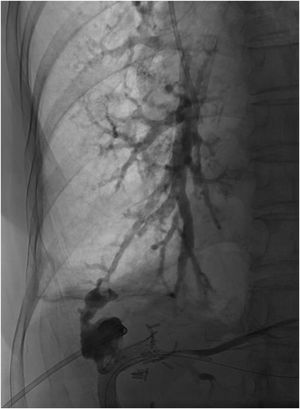

Mujer de 60 años con antecedentes de hepatectomía derecha por cáncer colorrectal metastásico que presenta recidiva en el borde de sección hepático, tratada con radioterapia externa tras la que desarrolla una ictericia obstructiva secundaria a una lesión actínica de la vía biliar intrahepática. Portadora de catéter de derivación biliar externo, tras varios procedimientos intervencionistas se consigue recanalizar la vía biliar mediante abordaje combinado endoscópico y percutáneo (rendez-vous). Posteriormente, la paciente desarrolla una fístula biliar que tras varios procedimientos intervencionistas con colocación de varias prótesis biliares recubiertas evoluciona hacia el desarrollo de una fístula biliobronquial (fig. 1).